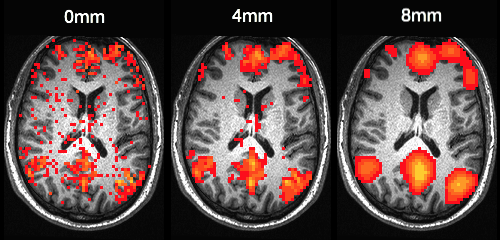

Smoothing kernels CPAC pipeline